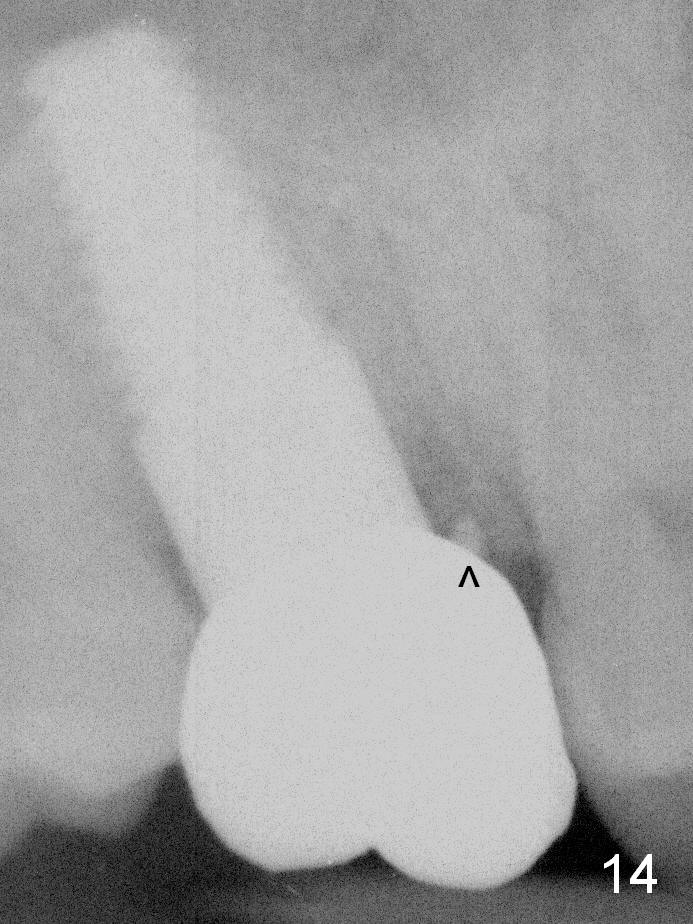

The implant remains stable 2.5 months postop without abnormal bone resorption (Fig.9). Since the provisional has dislodged on several occasions, impression is taken for final restoration. When the provisional is removed 3 months postop, the margin of the restoration is shown to be subgingival (Fig.10 arrowheads), but is distinctly separated from the gingiva. This is due to the presence of the provisional (its margin were fabricated slightly deeper). The provisional is also intentionally fabricated slightly larger than the final restoration. When the latter is cemented, there is space to remove extra cement trapped subgingivally (Fig.11). No cement is visible post cementation (Fig.12 (C: crown)). Eighteen months post cementation, the patient returns for recementation. After laser gingivectomy and Panavia resin bonding, PA shows residual cement (Fig.13 ^). After repeated removal with Piezo scaler and explorer, the residual cement appears to be smaller, which is ignored at the time of X-ray taking (Fig.14 ^). More dismayed is tight mesial contact. Water pik is recommended. When peri-implantitis develops later on, make an incision for cement removal. If the crown is dislodged soon, check whether the existing abutment is loose, remove acrylic in the access hole and remove the abutment. Install a new 4x3 mm one. Trim the abutment carefully and more on the opposing tooth.